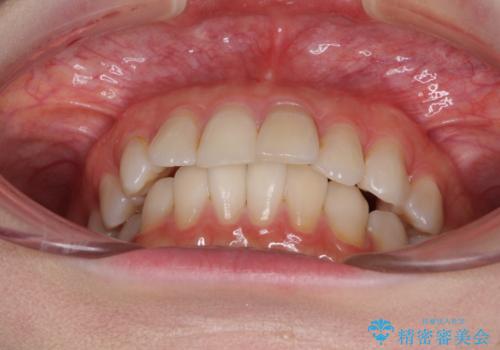

前歯の突出感とデコボコをインビザライン矯正で改善

- 上下前歯の突出感とデコボコを気にして来院された患者様です。

インビザラインによる上下歯列の側方拡大と後方移動、IPR(歯と歯の間を削る)にるスペースの獲得により歯列を整えることとしました。

骨格的な左右差があったため、上下の正中を合わせることができませんでした。

骨格の差は改善できないため、奥歯の咬み合わせに物足りなさを感じましたが、奥歯の咬み合わせによる不自由はなく、口元の突出感も改善することができました。